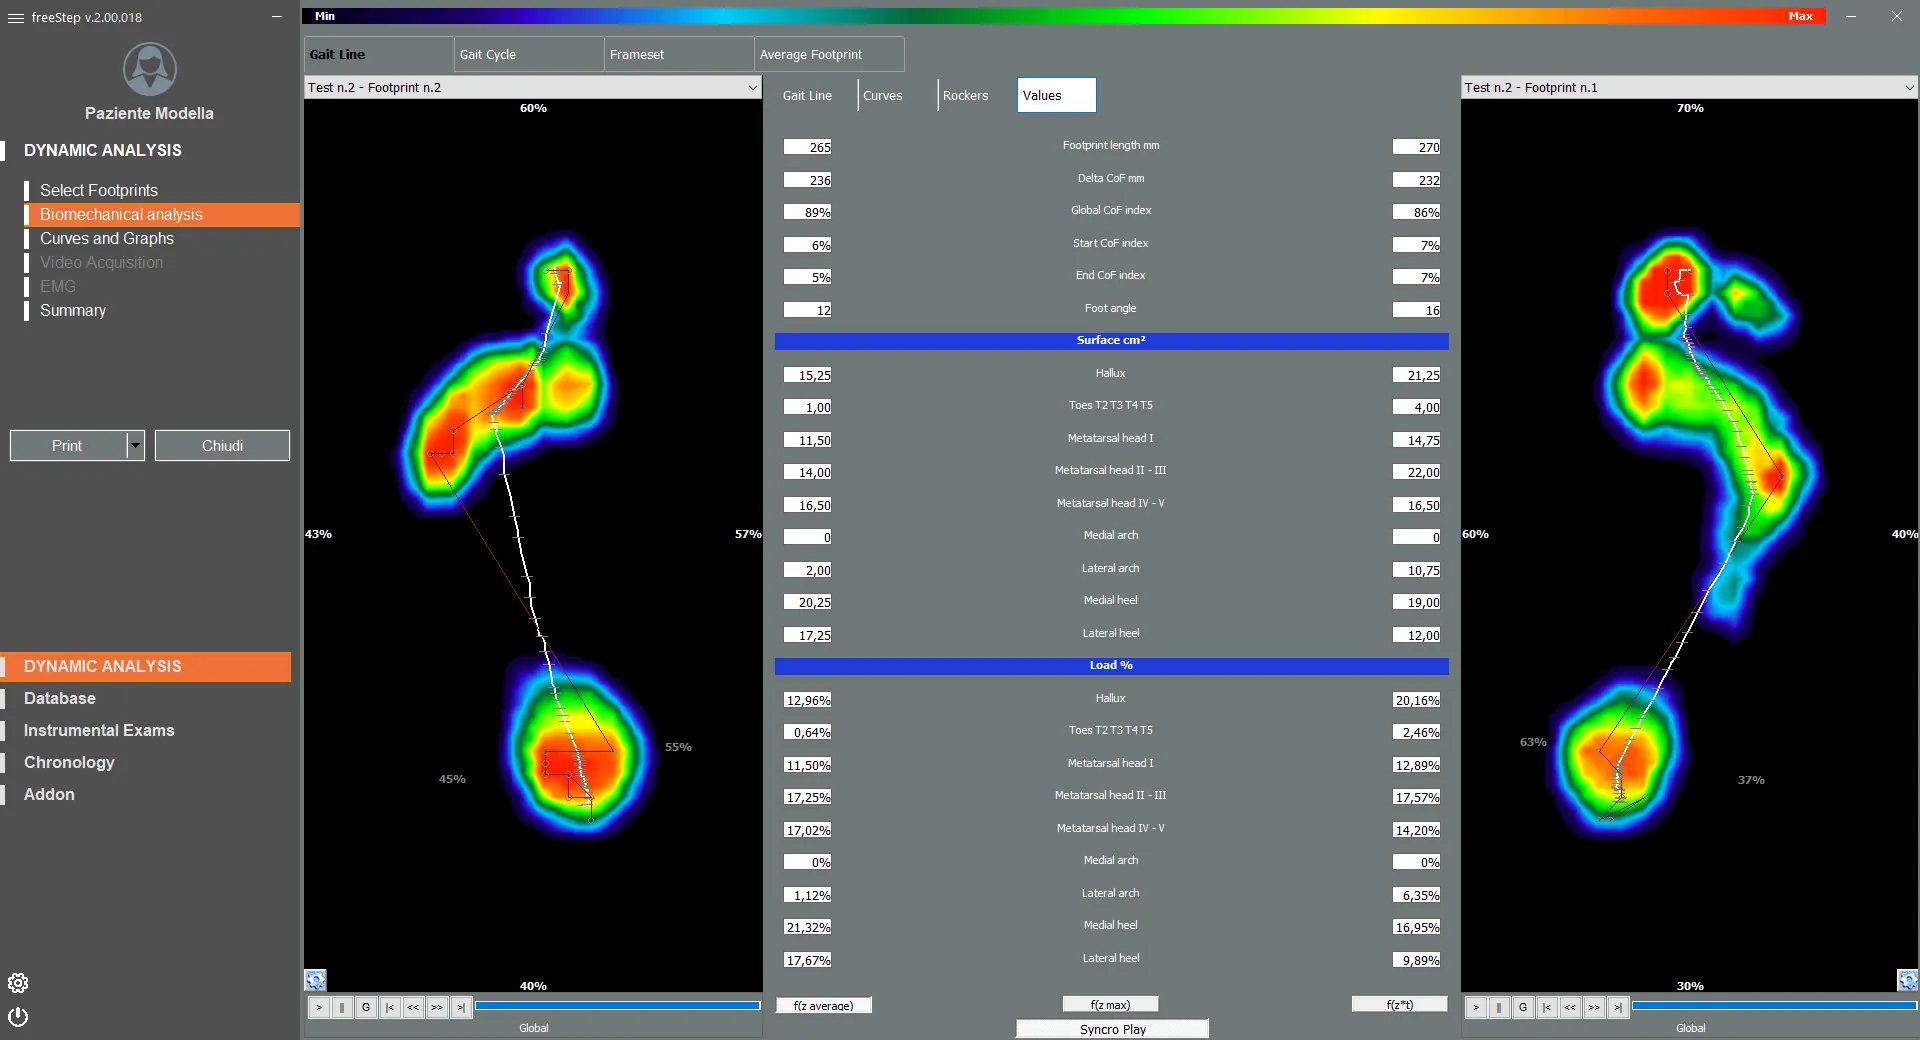

- Поверхности опоры

- Распределение нагрузки

- Оси и углы стопы

- Длина стопы

- Скорость

- Линия походки